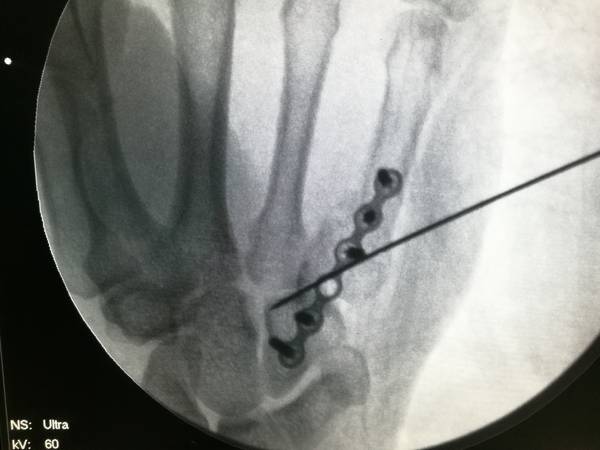

第五掌骨基底骨折

不稳定,可行接骨板跨关节固定

个人认为,克氏针横行固定第四五掌骨更实用,更经济,更简便

IMG_20190107_195955.jpg